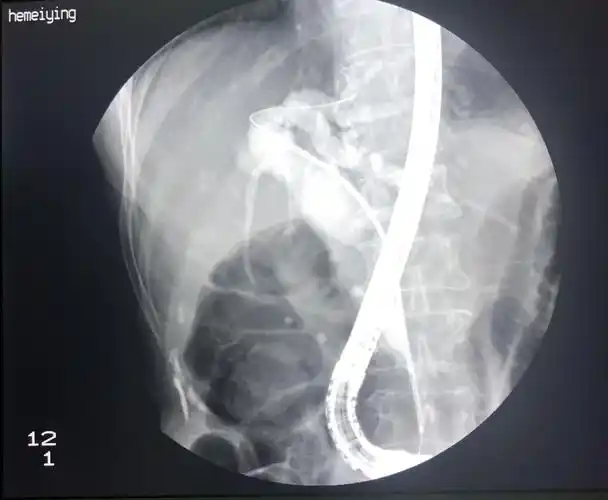

胰管支架按照这一方案,手术顺利进行.

胆道支架及胰管支架